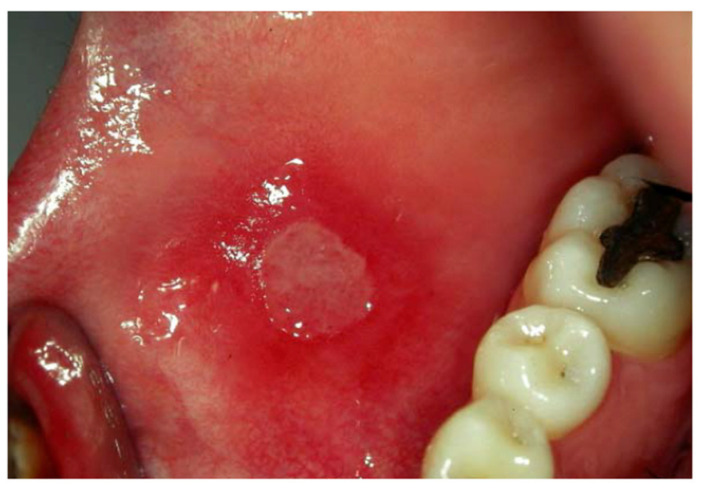

Injury to the oral mucosa (Figure 1) during orthodontic treatment is extremely common [1,2]. Patients with fixed orthodontic braces frequently complain about the presence of sharp edges that irritate the labial or buccal mucosa. Indeed, traumatic oral ulceration (TOU) is one of the most frequent side effects of orthodontic treatments. The TOU incidence reported in the literature is between 60% and 81% of patients wearing braces; TOU onset is mainly in the first few weeks of treatment [1,2,3]. About 47% of adults reported that TOUs are the most troublesome aspect of orthodontic treatment, while 29% of adolescents report that ulcers are the second most troublesome aspect of treatment [1,2]. Pain is part of the inflammatory phase, which usually occurs within 24 h of the onset of the injury. During the first two days after the onset of UTO, patients have difficulty eating and tend to self-medicate the lesion [3]. After removal of the damaging agent, TOUs normally heal within 10–14 days [4]. TOUs can limit chewing and speaking functions and have a negative effect on the patient’s quality of life at the beginning of the therapy, thus compromising good compliance during the orthodontic treatment. Few epidemiological studies have been conducted regarding the clinical course of TOU [2,3,4,5].

Figure 1.

Aphthous lesion in an adult patient.

Aphthous lesion (Figure 1) is an oral mucosal inflammatory lesion that affects all different oral tasks, from feeding to speaking, damaging the quality of life (QOL) of patients, especially during orthodontic fixed therapies [11].